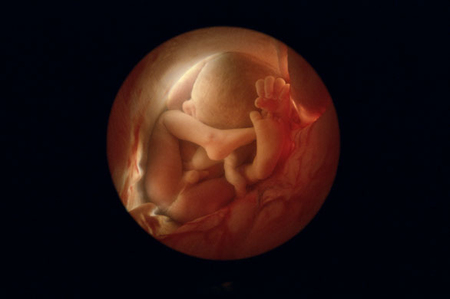

Вот сегодня наткнулась на эти фото.

Абалдееееть......Ведь из ничего.......И человек........

Я всегда поражалась этому чуду.....